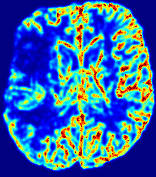

Slice #1Slice #2Slice #3Slice #4Slice #5Slice #6𝐕gt𝟐subscriptnormsuperscript𝐕gt2\|\bf{V}^{\text{gt}}\|_{2}Refer to captionRefer to captionRefer to captionRefer to captionRefer to captionRefer to caption𝐕est𝟐subscriptnormsuperscript𝐕est2\|\bf{V}^{\text{est}}\|_{2}Refer to captionRefer to captionRefer to captionRefer to captionRefer to captionRefer to captionRefer to caption1.51.51.51.21.21.20.90.90.90.60.60.60.30.30.30.00.00.0(mm/s)𝑚𝑚𝑠(mm/s)Destsuperscript𝐷estD^{\text{est}}Refer to captionRefer to captionRefer to captionRefer to captionRefer to captionRefer to captionRefer to caption0.0150.0150.0150.0120.0120.0120.0090.0090.0090.0060.0060.0060.0030.0030.0030.0000.0000.000(mm2/s)𝑚superscript𝑚2𝑠(mm^{2}/s)

Figure 14: PIANO identifiability testing: advection imaging via advection-diffusion. Top row shows 𝐕gt2subscriptnormsuperscript𝐕gt2\|{\bf{V}}^{\text{gt}}\|_{2} used for simulating ground truth pure advection. Rows below show the estimated 𝐕est2subscriptnormsuperscript𝐕est2\|{\bf{V}}^{\text{est}}\|_{2} and Destsuperscript𝐷estD^{\text{est}} on corresponding slices. Note that the plotted value scale for Destsuperscript𝐷estD^{\text{est}} is 0.01 of that for 𝐕gt2subscriptnormsuperscript𝐕gt2\|{\bf{V}}^{\text{gt}}\|_{2} and 𝐕est2subscriptnormsuperscript𝐕est2\|{\bf{V}}^{\text{est}}\|_{2}.

We use the same ‘Advection Imaging’ simulation of Sec. 4.2.1 as the concentration dataset for PIANO. However, instead of modeling pure advection (Eq. 15), we let PIANO estimate both velocity 𝐕estsuperscript𝐕est{\bf{V}}^{\text{est}} and diffusivity Destsuperscript𝐷estD^{\text{est}} via the advection-diffusion PDE (Eq. 2) underlying the proposed PIANO model. Fig. 14 shows the estimated 𝐕est2,subscriptnormsuperscript𝐕est2\|{\bf{V}}^{\text{est}}\|_{2}, and Destsuperscript𝐷estD^{\text{est}} fields for one patient. Although PIANO has the freedom to estimate both a velocity and a diffusivity field from pure advection, PIANO differentiates well between advection and diffusion: the estimated 𝐕est2subscriptnormsuperscript𝐕est2\|{\bf{V}}^{\text{est}}\|_{2} successfully reproduces the ground truth 𝐕gt2subscriptnormsuperscript𝐕gt2\|{\bf{V}}^{\text{gt}}\|_{2} governing the simulated advection process, just as it already did in the ‘Advection Imaging via Advection’ test (Fig. 12). More importantly, the estimated diffusivity Destsuperscript𝐷estD^{\text{est}} is orders of magnitudes smaller than 𝐕est2subscriptnormsuperscript𝐕est2\|{\bf{V}}^{\text{est}}\|_{2}, indicating the estimated diffusion is negligible compared to the estimated advection, which is highly consistent with the underlying pure advection of the simulated data.